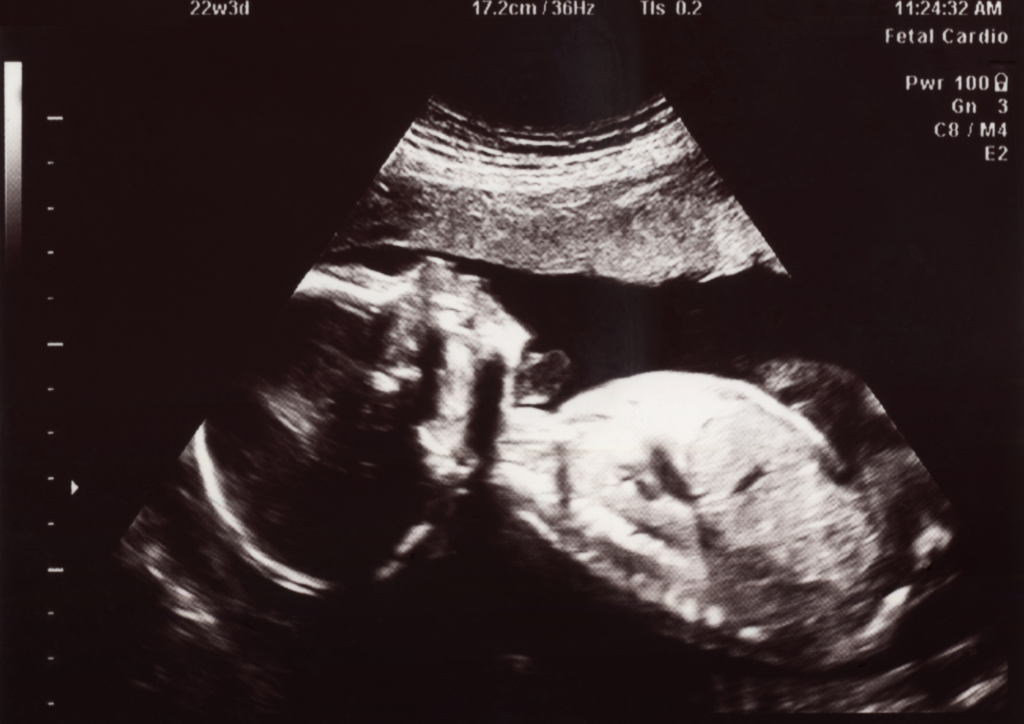

What does 22 weeks pregnant look like?

Other questions asked were:

- How does 22 weeks pregnant look?

- How does 22 weeks pregnancy look like?

- how does 22 weeks pregnant look like?

Here’s what 22 weeks pregnant looks like: